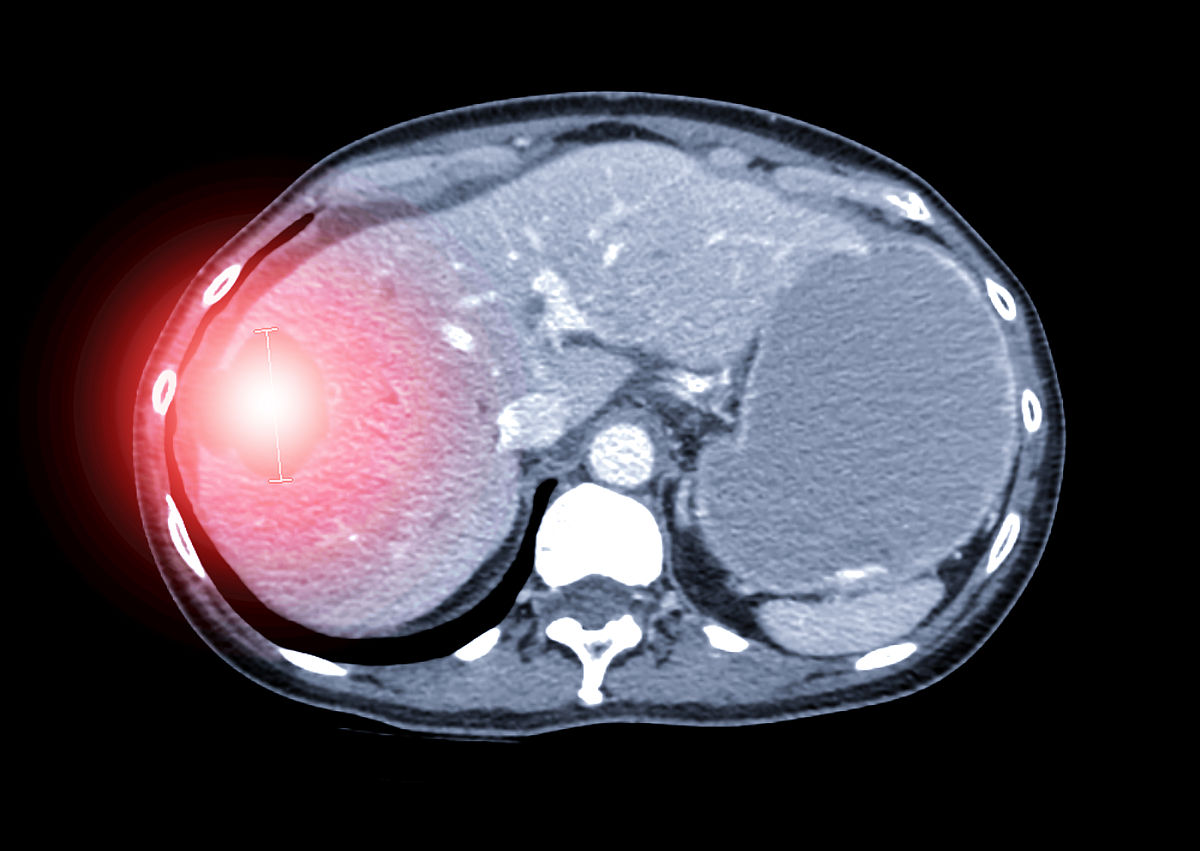

肝 低密度 不强化

这种情况可能是指肝脏CT或MRI检查中,肝脏组织呈现低密度(即比正常肝组织更淡)且没有明显强化的情况。可能的原因包括肝脏脂肪变性、肝囊肿、肝血管瘤等,需要结合具体病史和其他检查结果进行综合分析和诊断。建议及时就医并进行必要的检查和治疗。